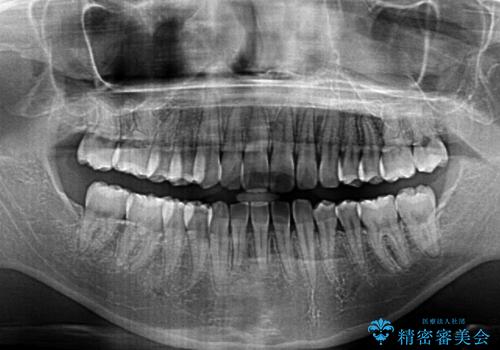

奥歯のかみ合わせも妥協しない インビザライン治療

- 歯のがたつきを主訴に来院。

左右とも奥歯のがたつきがあり、左奥はすれ違っていました。

また、右奥は反対咬合になっていました。

患者様が気づかない範囲で妥協して終わるということをせず、しっかり奥歯に部分矯正を用いて大きな問題を解決してからインビザライン治療に入りました。

下の前歯を一本抜歯しています。(抜歯の本数は最小限にしています。)